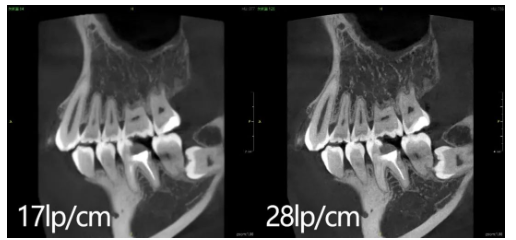

派CT还搭载了有方自主研发的低剂量成像核心算法,以确保低剂量模式下图片的清晰程度。有此算法的加持,派CT的大视野重建时间仅需2.6s,图像分辨率高达28lp/cm,无需增加X射线剂量,即可获得当下行业内最高分辨率的CBCT图像。

▲28线对成像与17线对成像对比